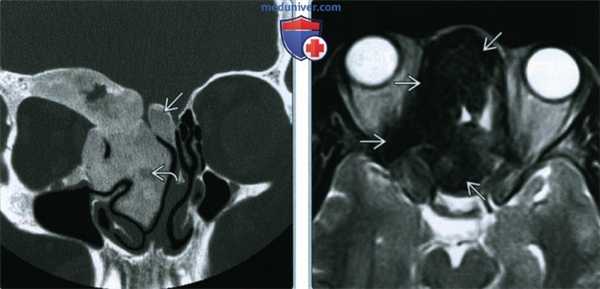

Воспалительные изменения слизистой оболочки верхнечелюстной пазухи, существующие в течение длительного времени, вовлекают в процесс костную стенку. На компьютерных томограммах отмечается утолщение костной стенки в костном режиме и появление «оптического эффекта» — уплотнение стенки в 1,5—3 раза за счет отека надкостницы — при просмотре в мягкотканом режиме (рис. 1, а, б) [9]. При одностороннем процессе, характерном для одонтогенного поражения, на контралатеральной интактной стороне такого эффекта не определяется.

Рис. 1. Рентгеновская компьютерная томограмма околоносовых пазух. Коронарная проекция: мягкотканное окно (а) и костное окно (б).

В костном режиме программы просмотра изображений утолщение костных стенок верхнечелюстной пазухи определялось в 21% случаев (рис. 2, 3), что указывает на хронический характер воспаления. «Оптический эффект» в мягкотканном режиме программы просмотра диагностических изображений определялся у 30,7% больных, что указывает на вовлечение надкостницы.